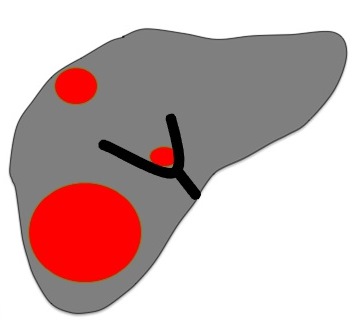

- Leziuni mai mici de 3 cm - Tinta ideala a tratamentului cu RFA este reprezentata de un nodul hepatic <3 cm, fara topografie subcapsulara sau care nu este in apropierea unor vase mari

- O zona de ablatie suficienta pentru un tratament curativ fara riscuri semnificative se poate obtine in cazul nodulilor <5 cm (cu minim 2 aplicatii) si a maxim 4 noduli <3 cm.

In cazul tumorilor mai mari de 3 cm sau leziuni multiple, s-a demonstrat ca tratamentele combinate (chemoembolizare plus tehnici de ablatie) sunt mai eficiente fata de terapiile unimodale. Combinatiile de terapii (RFA+TACE) pot fi o solutie foarte utila in cazul nodulilor de mari dimensiuni sau in cazul recidivelor post RFA.